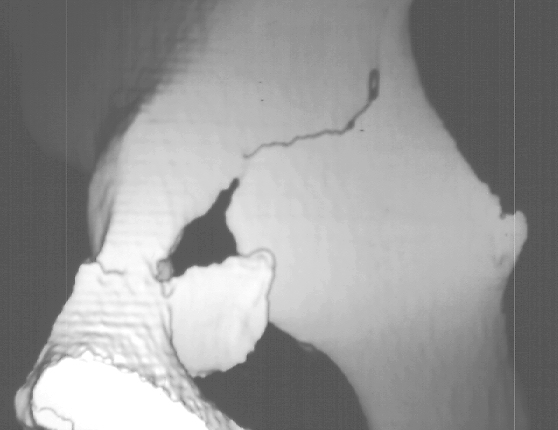

Radiographs revealed a vertical buckle fracture of the right inferior sacrum, oblique fractures of the superior and inferior rami on the right and a fracture through the medial acetabulum. Obturator and iliac oblique inlet and outlet pelvic views, and a thin cut CT with 3-D reconstruction of the acetabulum were performed. These elucidated a comminuted anterior wall with fracture line extending to the posterior column. The posterior column was non-displaced. The pelvic fracture was non-displaced.

1. Right T-shaped acetabular fracture with anterior wall comminution.